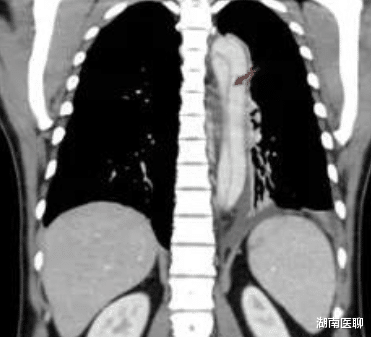

为了患者安全 , 李主任直接安排了增强CT检查 , 结果证实就是“主动脉夹层Stanford B型” , 立即建议到心血管十八病区住院治疗 , 入院后血压:左上肢222/142mmHg右上肢216/138mmHg , 凶险至极!

那是否考虑主动脉夹层?还是说背痛是因为胸腰椎压缩性骨折引起?根据患者症状 , 结合血压181/103mmHg, 唐主任认为首先应该排除致命性心血管疾病“主动脉夹层” , 马上建议患者至心血管内科十八病区进一步诊治 , CTA明确诊断为B型夹层 。